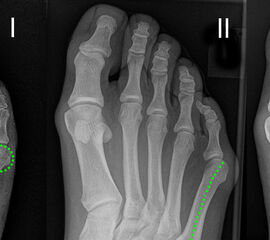

Die Ulcera im Bereich der Kleinzehen konzentrieren sich beim Diabetes-Patienten in der Regel auf zwei Areale. Das Tip-Toe-Ulkus bezeichnet ein Ulkus an der Spitze der Kleinzehen bzw. an der Zehenbeere. Dieses Ulkus ist häufig auch mit rezidivierenden Paronychien vergesellschaftet. Die zweite Risikozone findet sich dorsale des proximalen Interphalangealgelenkes (Abb. 2 A+B).

Im Rahmen der Neuropathie kommt es zu einem erhöhten Tonus der Zehenflexoren. Die zunehmende Destruktion der plantaren Platten im Bereich der Metatarsophalangealgelenke (MTP-Gelenke) unterstütz zusätzlich die Entwicklung von Krallen- bzw. Hammerzehen. Aus der Flexionsstellung im DIP-Gelenk resultiert eine vermehrte Druckbelastung im Bereich der Zehenbeere, was zu rezidivierenden Ulcera führen kann. Sowohl bei Hammerzehen als auch bei Krallenzehen kann es zu Druckulcera im Bereich der proximalen Interphalangealgelenke kommen. Ungeeignetes Schuhwerk mit einem zu engen Zehenraum tragen ebenfalls zur Ulkus Entstehung bei.